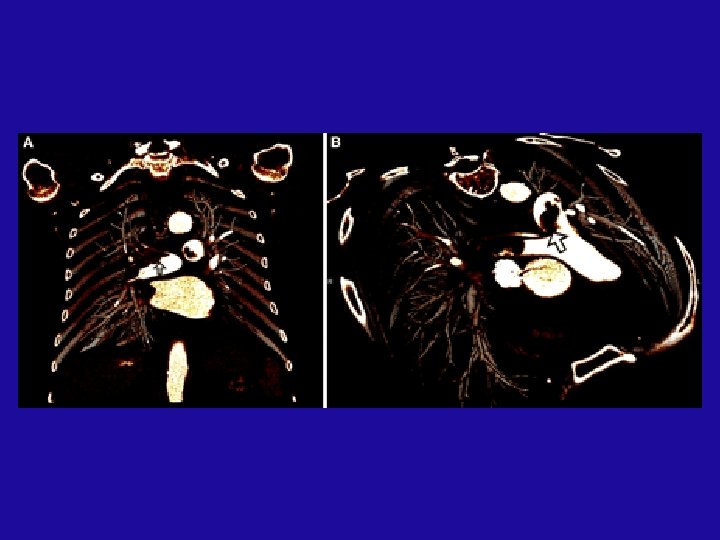

Risk stratification 4 - Spiral CT A- RV dilatation relative to LV size. RV dilatation and pulmonary vascular obstruction (≥ 40%) on chest CT is a predictor of eary death after APE (Circulation 2005; 235(3): 798 -803) B- Saddle or large proximal thrombus

Massive PE Note the large thrombus burden in the main pul. branches